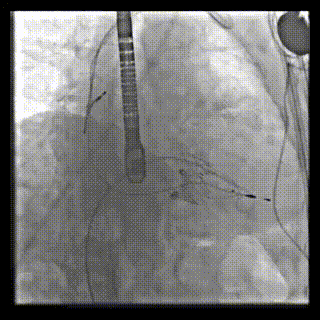

本周三例接受LuX-Valve Plus經(jīng)血管三尖瓣置換術(shù)的患者中,第一例患者為冠狀動(dòng)脈旁路移植術(shù)+Bentall+二尖瓣成形術(shù)后;第二例患者為永久起搏器植入術(shù)后,存在跨三尖瓣導(dǎo)線;第三例患者合并房顫、房缺及左心耳封堵術(shù)后。

三例患者入院后,葛均波院士團(tuán)隊(duì)周達(dá)新教授、潘文志教授、張?jiān)床┦?、陳莎莎博士及心超室的潘翠珍教授、李偉教授?duì)患者的情況進(jìn)行詳細(xì)評(píng)估和討論,最終決定為三例患者選擇LuX-Valve Plus40mm、50mm和50mm型號(hào)的瓣膜進(jìn)行手術(shù)治療。手術(shù)后即刻拔除氣管插管,術(shù)后患者三尖瓣反流癥狀得到顯著改善,復(fù)查心超結(jié)果顯示人工三尖瓣瓣膜支架固定穩(wěn)定,瓣葉關(guān)閉形態(tài)未見異常,未見明顯反流。